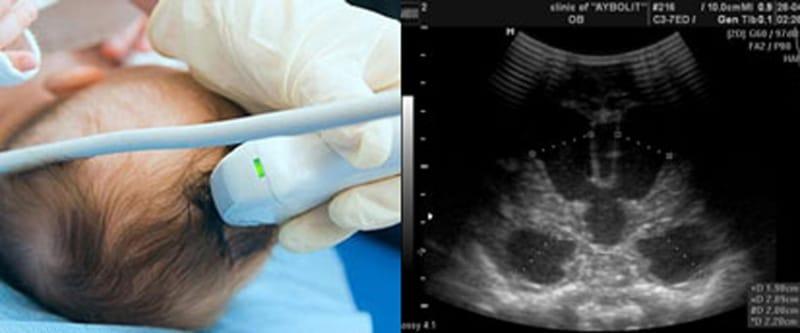

Нейросонография позволяет выявить повреждения мозга, структуру пространств, заполненных спинномозговой жидкостью, состояние сосудов, обнаружить отеки. Исследование проводится до выписки из родильного дома, в 1 месяц жизни, при необходимости повторяется позднее. Повторное исследование позволяет прояснить динамику и влияние лекарств.